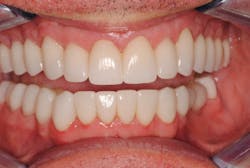

After two months and careful evaluation in the patient-approved provisional restorations, this case was completed. The patient was restored completely (except for two acceptable implant crowns on tooth Nos. 19 and 20) with full-zirconia crowns on the posterior teeth and zirconia with minimal facial layering on the anterior teeth. He has been successfully restored for two years (figures 5 and 6) to date.

Figure 5: After treatment

Figure 6: After treatment